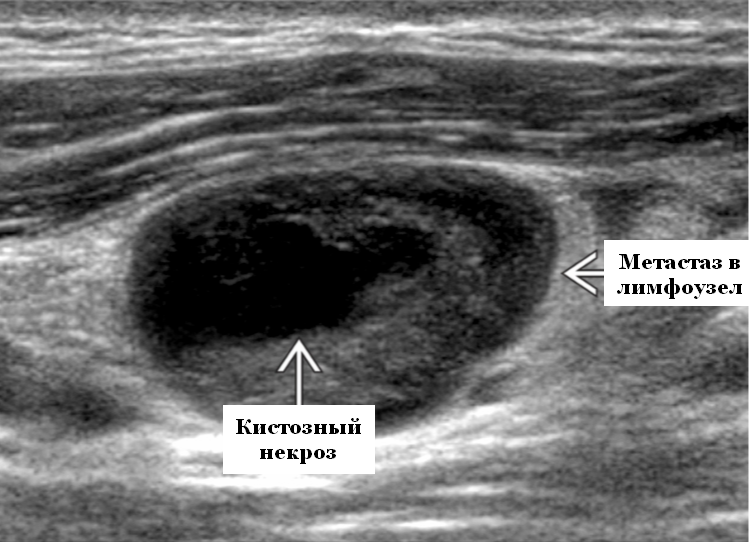

УЗИ лимфоузлов при лимфоме Ходжкина

Раздел: Образы вокруг